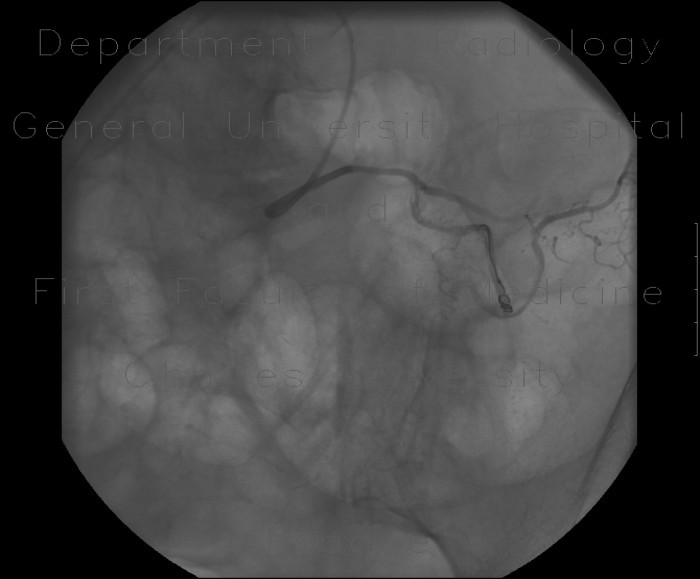

Embolization for vascular lesions 49 Fig. 6. Right external carotid arteriogram, lateral view. Note ab- errant course of maxillary and transverse facial arteries. ... Fetch Content